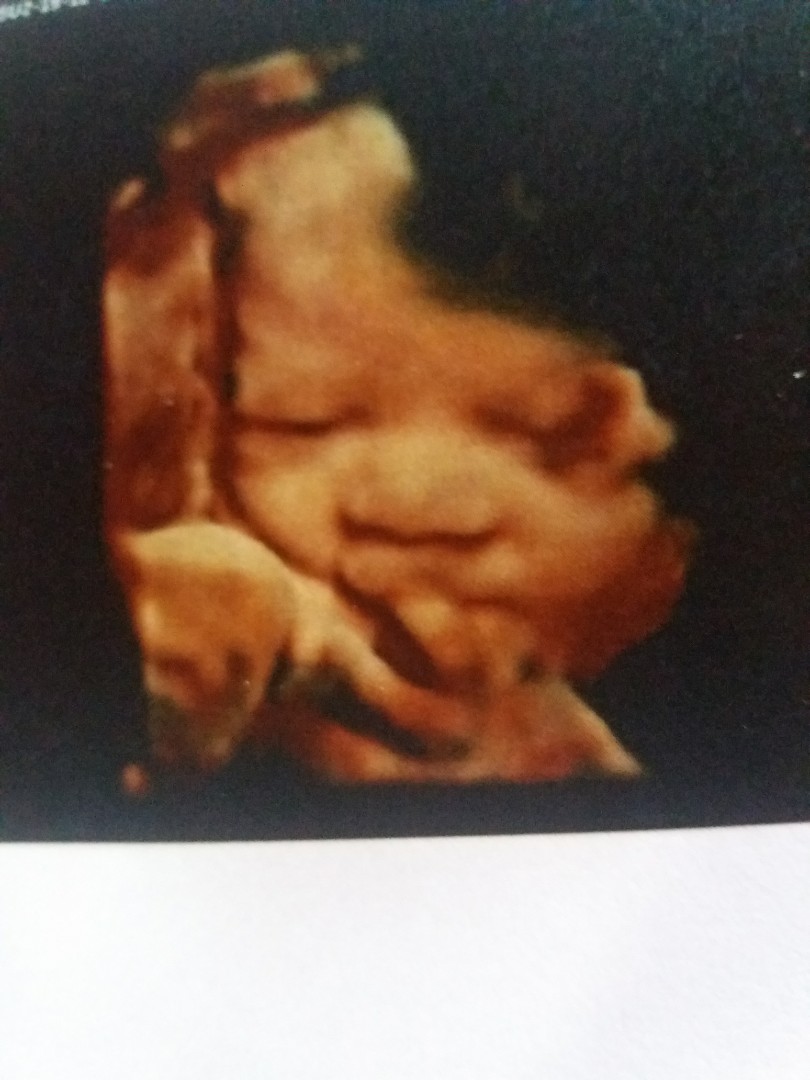

กว่าจะได้แบบนี้ ลุ้นตั้งนาน

ซาว2รอบกว่าจะยอมให้เห็นหน้า

ซาวด์ตอน27weekจ้า ตอนนี้33+2weekแล้ว